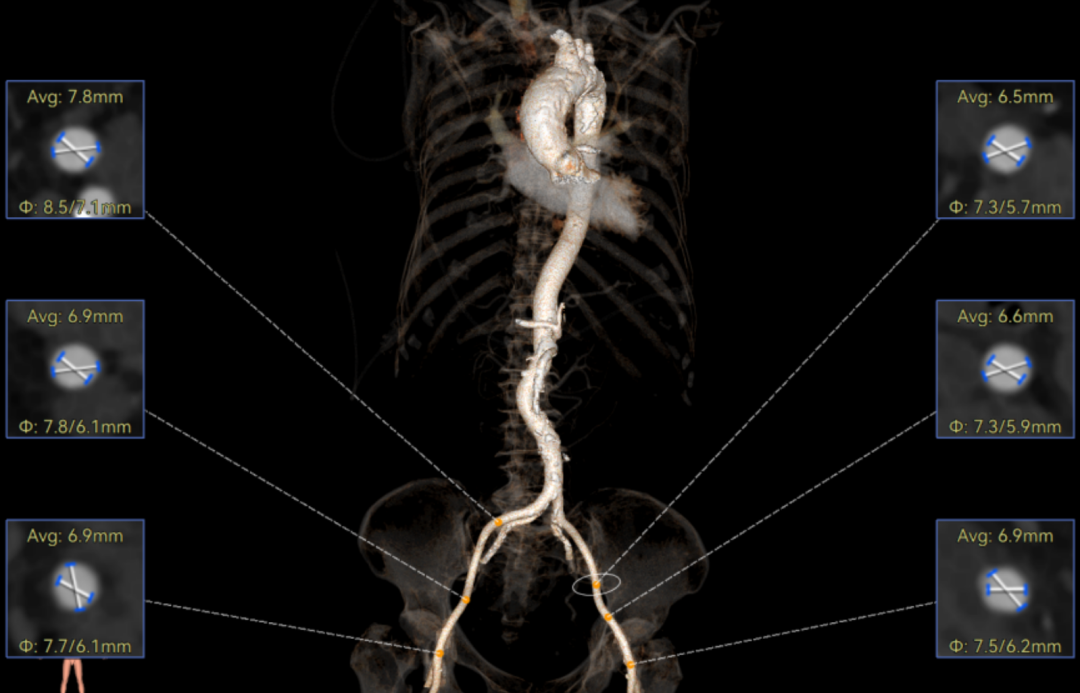

主动脉瓣环周长径21.9mm,小瓣环,LVOT直筒型结构;三叶瓣,左右融合(功能型二叶瓣),瓣叶轻微增厚并重度钙化,钙化主要分布在无冠窦瓣叶边缘及左右交界融合处,瓣上限制较重。

窦部空间适中,STJ内径偏小,升主动脉内径可。

外周双侧入路无明显迂曲、直径可容纳20F大鞘通过,双侧中分叉,穿刺需注意。主动脉弓角弓距可,髂总动脉及分支多处钙化,瓷化升主动脉,钙化由升主动脉蔓延至主动脉弓侧壁及弓顶弓底部,有一定卒中和夹层风险。

经过庄晓东教授团队分析,拟右股动脉作为主入路,使用可调弯长鞘建立通道,使用18mm球囊预扩,选择AV23号Prostyle A®瓣膜进行释放。